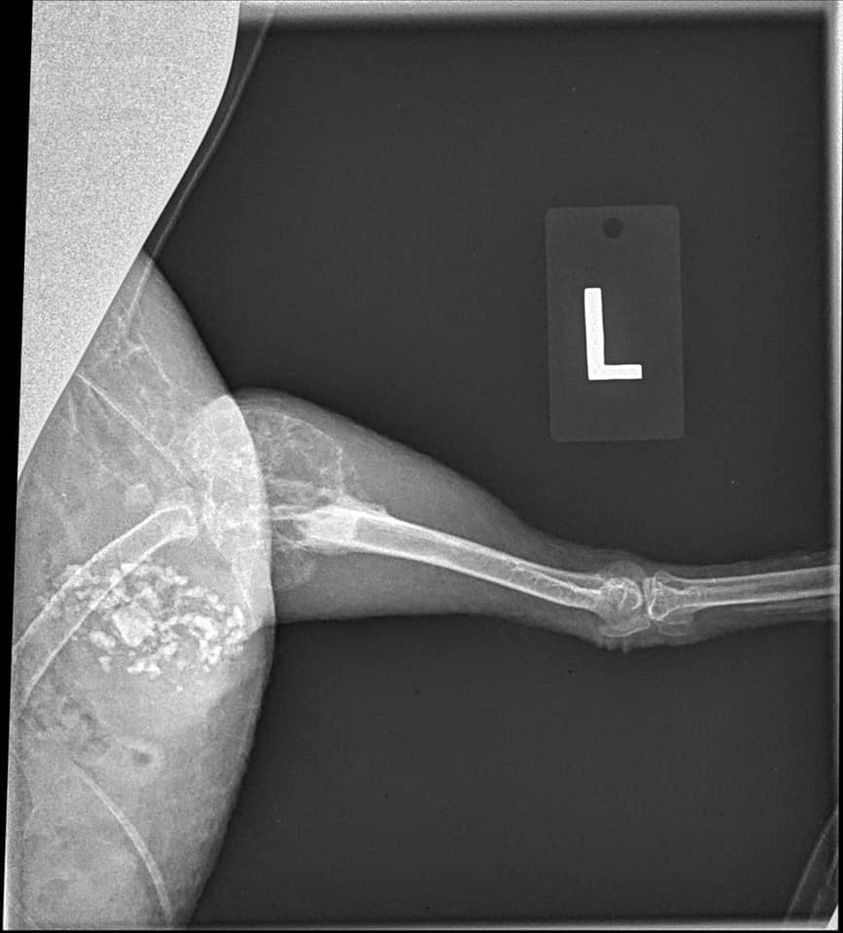

“Our Silkie hen has had a limp that has been getting worse over the last year. The vet took x-rays and sent them to a specialist who diagnosed a bone cyst in her leg and on her wing. She is now on Metacam, but we’re unsure where to go from here. The vet says we could do a biopsy of the cyst, but that would be in the $600-700 dollar range and we can’t afford that right now.”

Dr Bowes: The areas of deterioration in the wing and hip are not bone cysts. Osteosarcoma is one condition that eats bones, but is rare. Avian Tuberculosis is another possibility, but this case is more likely to be linked to bacterial arthritis caused by a Staphylococcus infection. There are multiple sites of deterioration in the wing (distal ulna) and no bone articulation in the hip making it increasingly difficult for the hen to walk. Recommendation: humane euthanasia.